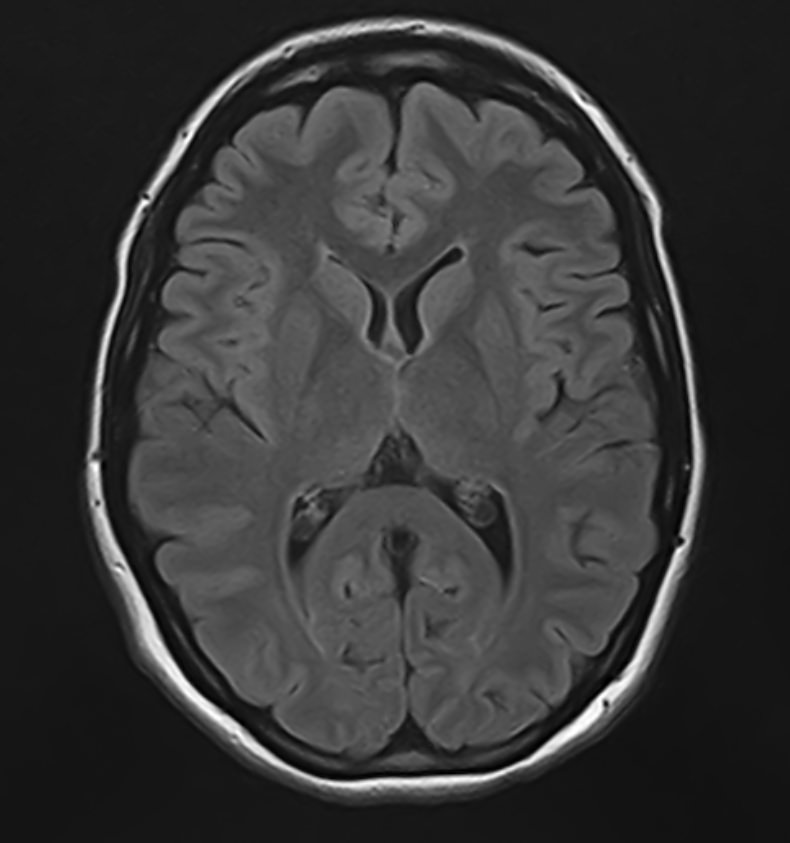

В клинике «Доступная медицина» можно пройти комплексное обследование, включающее в себя два протокола сканирования близко расположенных друг от друга анатомических областей – шейного отдела позвоночника и головного мозга.

Сканирование проводится на современном высокопольном магнитно-резонансном томографе закрытого типа TOSHIBA VANTAGE TITAN 1,5 Тесла, который делает послойные срезы в разных плоскостях с шагом от 1 мм и на основе полученных данных создает трехмерные изображения превосходного качества. Метод исследования позволяет в мельчайших подробностях визуализировать состояние всех структур головного мозга и шейного отдела позвоночника, что дает возможность выявлять патологические изменения на ранних стадиях и назначать своевременное лечение.